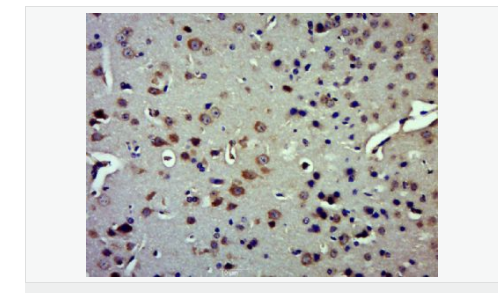

產(chǎn)品應(yīng)用WB=1:500-2000 ELISA=1:5000-10000 IHC-P=1:100-500 IHC-F=1:100-500 IF=1:100-500 (石蠟切片需做抗原修復(fù))

產(chǎn)品介紹Insulysin was identified nearly a century ago as an enzyme responsible for the degradation of insulin in cells, although the precise interactions between insulin and insulysin remain elusive. Human insulysin was cloned in 1988, and shown to be a 118 kDa protein that exists primarily as a homodimer, and perhaps also complexed with other molecules. The sequence is well conserved between humans, rats and mice, and the antibody recognizes these species. Insulysin is a metalloproteinase of the clan ME, family M16, which contains an active site HxxEH, a reversal of the canonical HExxH zinc binding motif. Considered a zinc metalloproteinase, the activity of insulysin can be blocked with EDTA or 1-10 phenanthroline. In addition to the active metalloproteinase domain, insulysin contains a second metalloproteinase site which is considered catalytically inactive, and is thought to assist in substrate binding. Insulysin is most closely related to the bacterial proteinase pitrilysin, (the human orthologue of which appears to be MPRP1) and the mammalian proteinsae nardilysin. Generally thought to be a cytoplasmic protein, insulysin has been isolated from many different tissues and cell lines, and can degrade intact insulin, insulin B chain, glucagon, denatured hemoglobin, alpha amyloid protein, TGF alpha and amylin. Recent work implicates insulysin in clearing beta amyloid plaques from the brain, and has generated much interest in Alzheimer’s disease research. The pH optimum for insulysin is basic, pH 8.5, which also distinguishes it from other metalloproteinases.